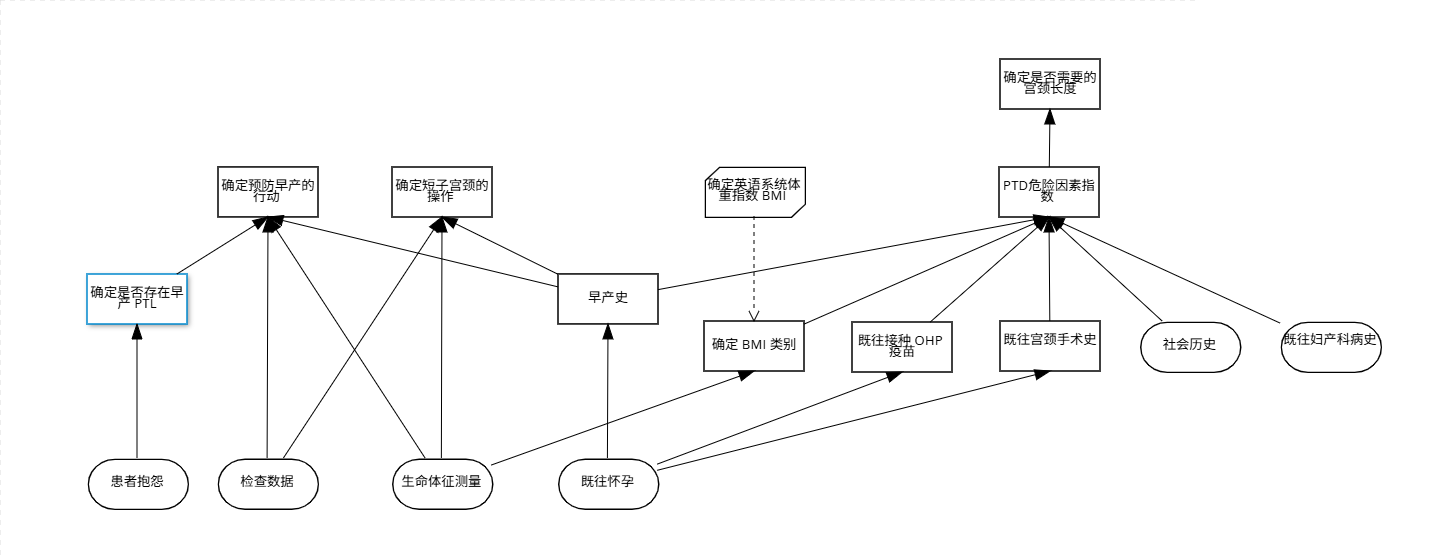

我们现在对早孕诊断的场景进行决策建模,首先在Together建模器中定义整个决策模型的数据结构。

然后在建模器画布拖拽图元,构建整个决策模型的逻辑结构。

输入数据

将数据结构与输入数据进行绑定

l “患者抱怨”即患者的症状口述信息

l “检查数据”即对患者初步的检查数据

l “生命体征测量”即对患者生命体征初步的检查数据

l “既往怀孕”即孕妇以往怀孕的诊疗信息

l “社会历史”即孕妇是否吸烟等信息

l “既往妇产科病史”即孕妇病史信息

业务知识函数

l “确定英语系统体重指数 BMI”即维基百科定义的体重指数计算公式。它有2个参数即身高、体重。使用文字表达式的盒装结构。

决策块

l “确定是否存在早产 PTL”即通过患者“患者抱怨”判断是否早产的可能性。使用文字表达式的盒装结构,其中用集合函数进行数据筛选。

l “确定预防早产的行动”即通过“检查数据”、“生命体征测量”输入数据,以及“确定是否存在早产 PTL”决策块来判断进一步的治疗措施。使用决策表的盒装结构。

l “确定短子宫颈的操作”即通过“检查数据”、“生命体征测量”输入数据,以及“早产史”决策块来判断进一步的治疗措施。使用决策表的盒装结构。

l “早产史”即通过2次循环“既往怀孕”中的怀孕周数、怀孕时长判断孕妇是否会早产。使用上下文的盒装结构,使用2个键值依次对数据进行筛选,最终判断。

l “确定BMI类别”即通过调用业务知识函数“确定英语系统体重指数 BMI”,判断体脂类别。使用上下文的盒装结构,有2个键值,一个计算患者BMI得分,另一个根据请结果匹配判断BMI类别,最终上下文输出结果。

l “既往接种 OHP 疫苗”即通过列表函数对“既往怀孕”进行筛选判断是否OHP注射判断是否既往接种OHP疫苗。使用文字表达式。

l “既往宫颈手术史”即通过列表函数对对“既往怀孕”进行筛选判断是否有既往宫颈手术史,使用文字表达式。

l “PTD危险因素指数”即创伤后应激障碍危险因素指数“早产史”、“确定BMI类别”、“既往接种OHP疫苗”、“既往宫颈手术史”、“社会历史”、“既往妇产科病史”进行统计,使用决策表。

l “确定是否需要的宫颈长度”即根据“PTD危险因素指数”数字判断,使用文字表达式。